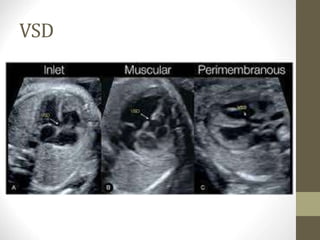

VSD

• Some lesions such as minor VSDs may be

missed.